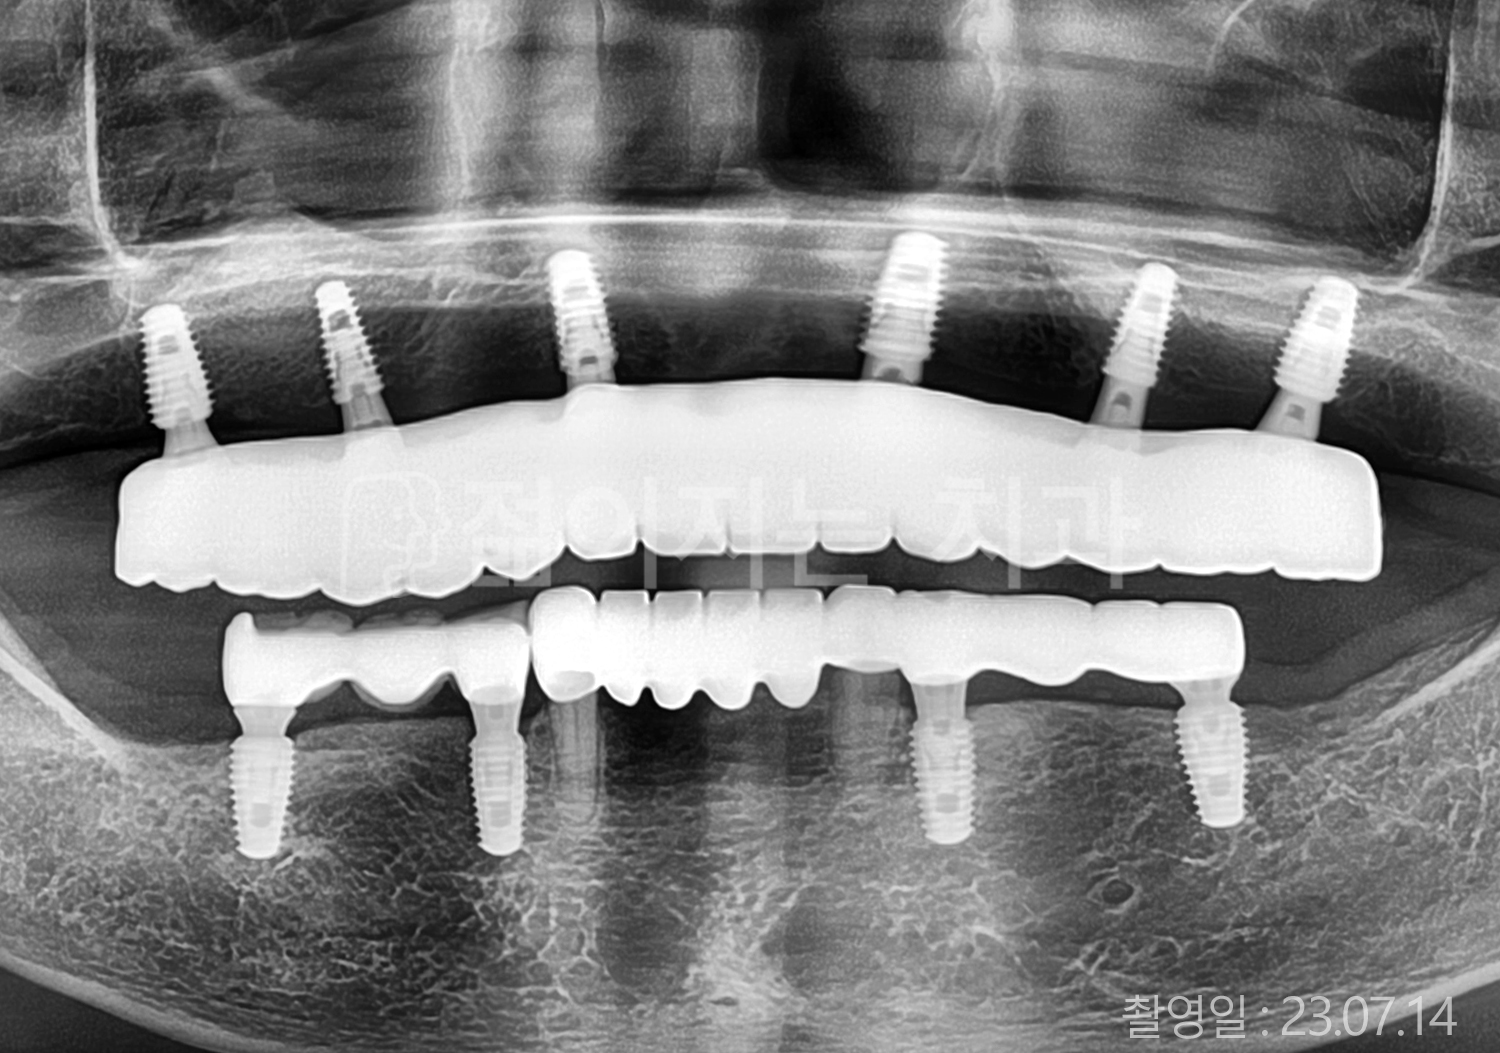

• 50대 전체치아 10개 이상 임플란트